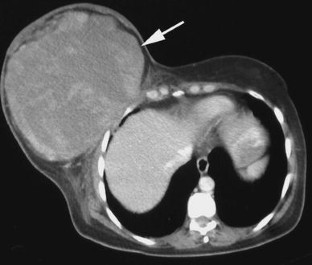

Fig. 1

Fig. 2